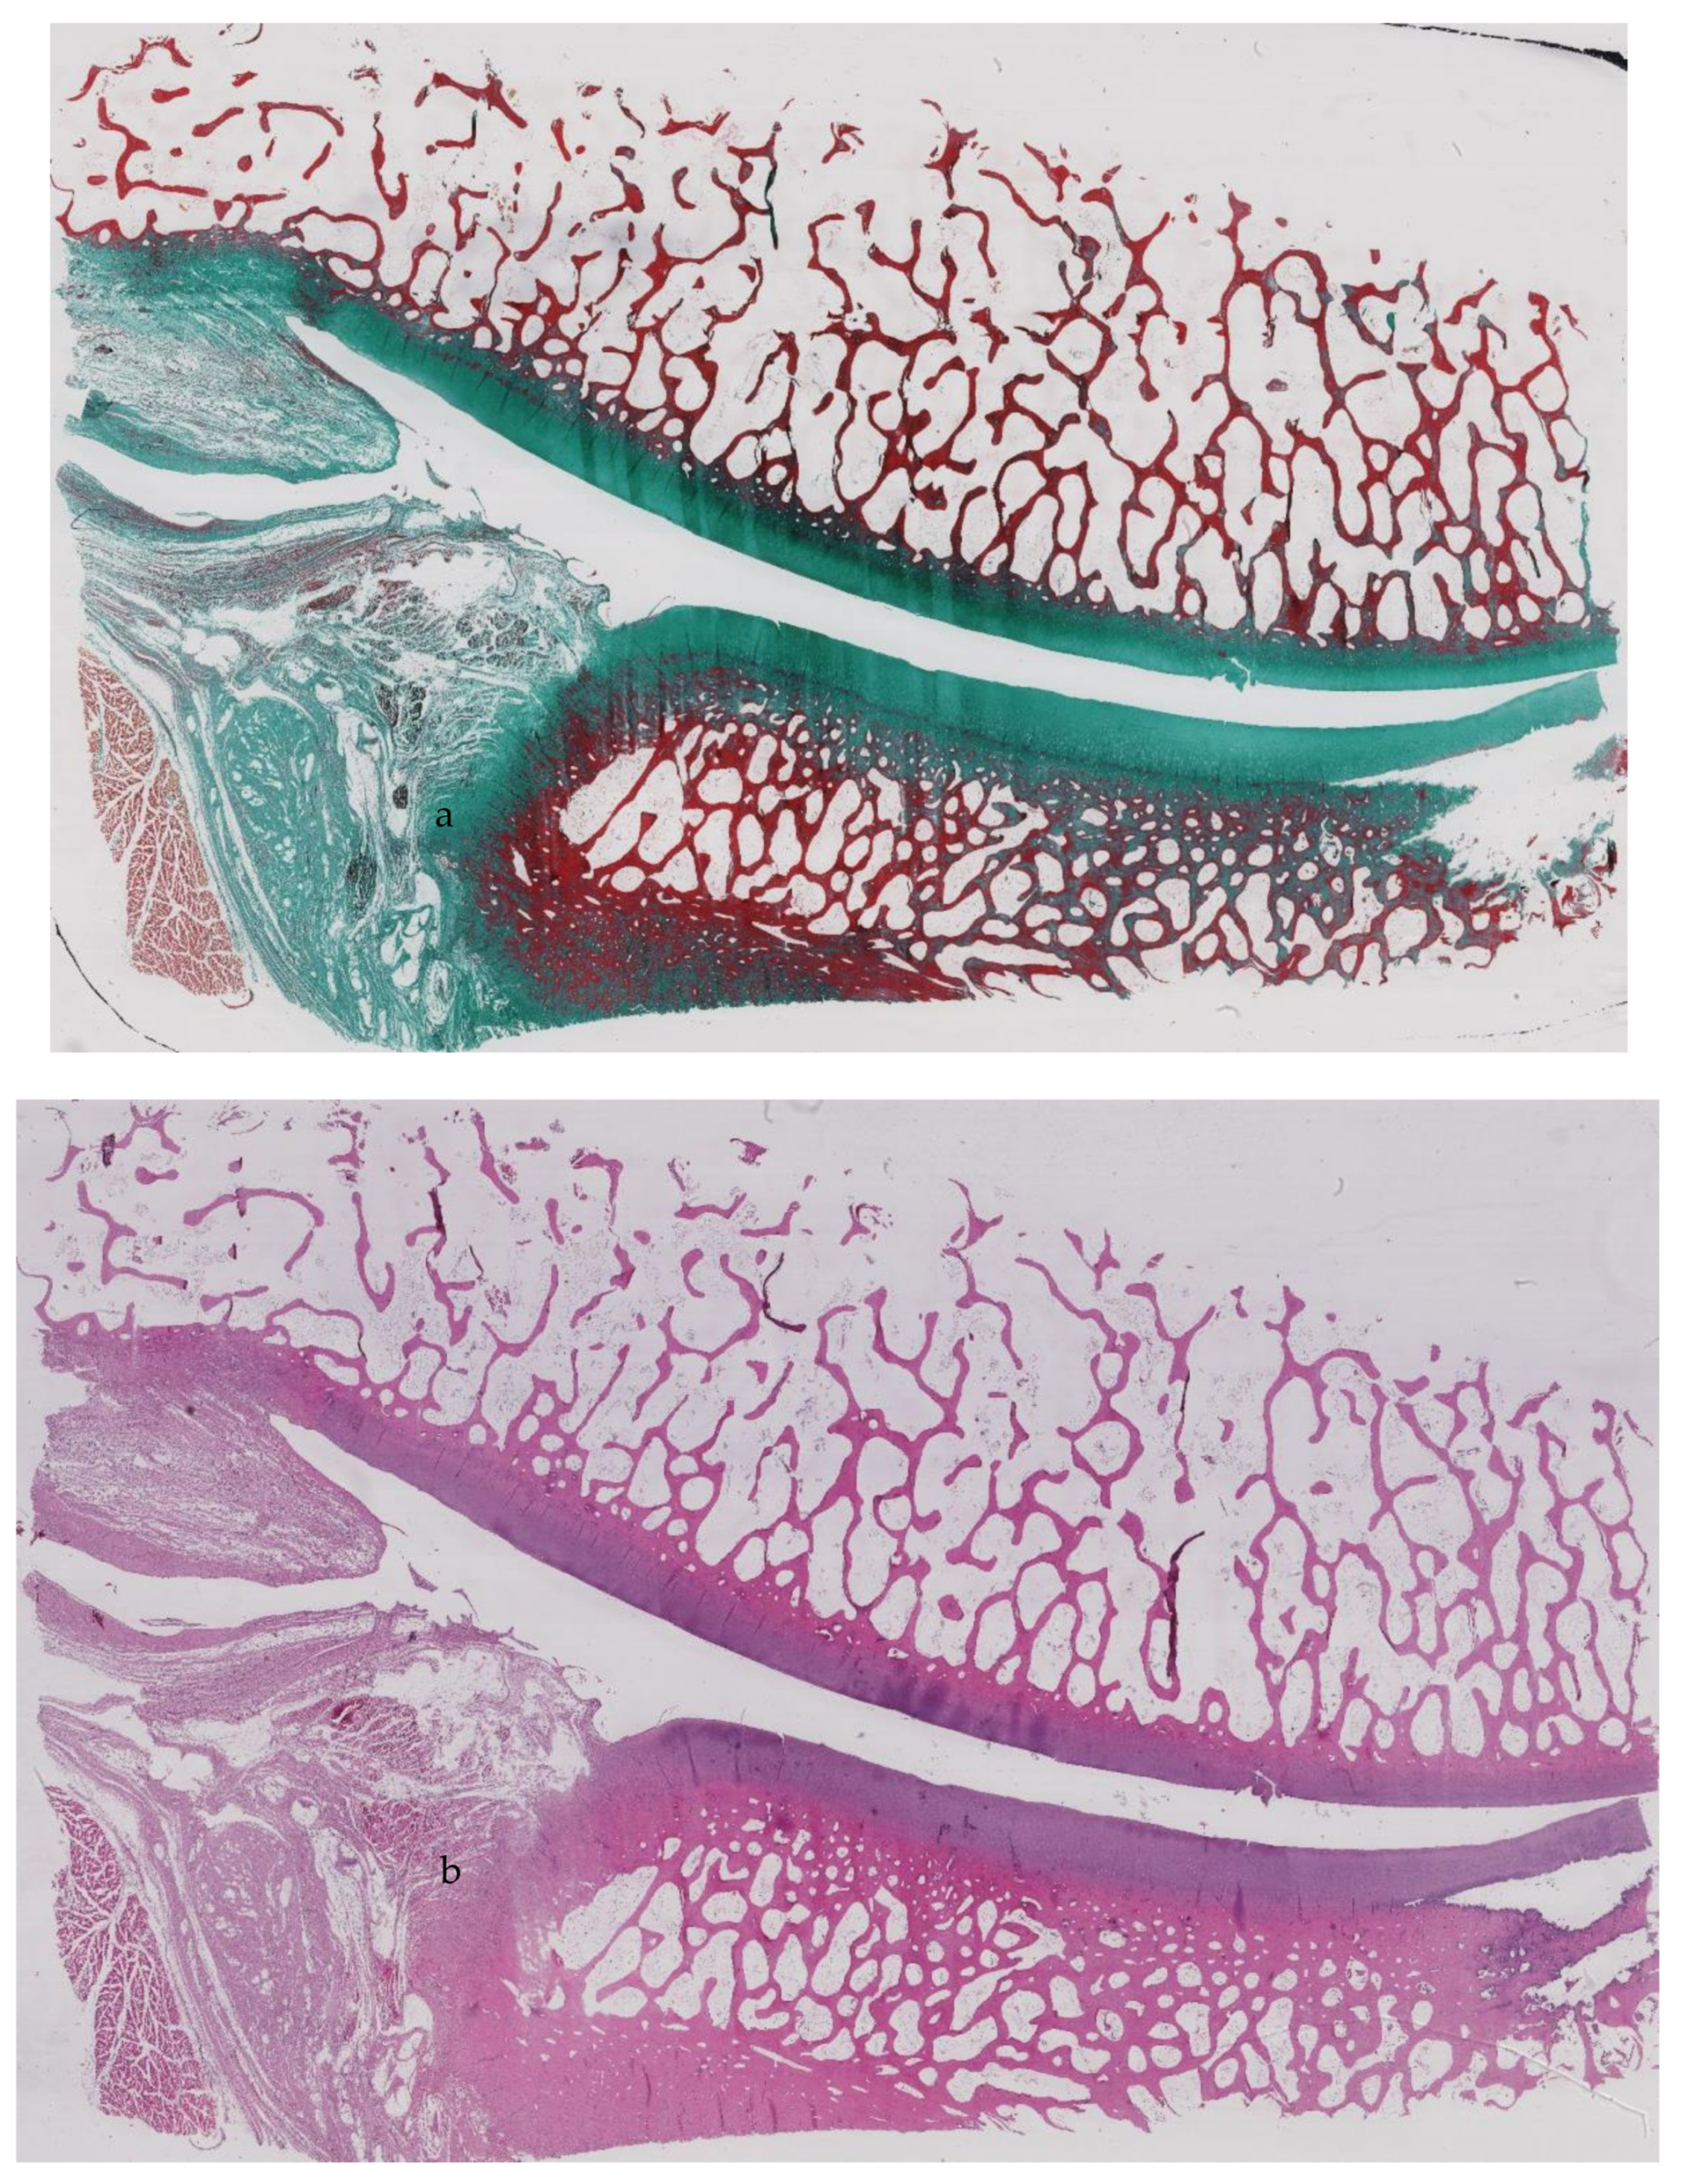

2.4. Shoulder Arthritis According to the Histopathologic Scoring System

3.3. Histological Assessment